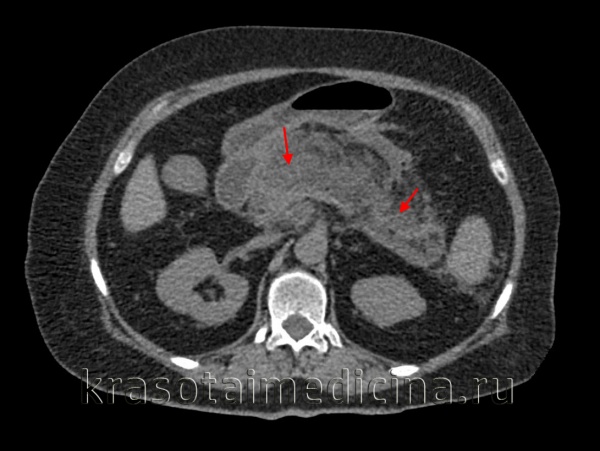

(Правый) У этого же пациента при КТ с контрастным усилением визуализируется гетерогенная низкоконтрастная поджелудочная железа, что соответствует картине интерстициального отечного панкреатита. Тело поджелудочной железы окружено зоной перипанкреатического отека; кроме того, в области хвоста железы определяется скопление секрета поджелудочной железы.

(Правый) У этого же пациента при КТ с контрастным усилением на поперечной томограмме наблюдается полное отсутствие контрастирования тела и хвоста поджелудочной железы, что характерно для панкреонекроза. Также определяется пери панкреатическое скопление жидкости, содержащее нежидкостные фрагменты, это указывает на острый некроз перипанкреатических тканей и формирование очага острого некроза.

(Правый) У того же пациента при КТ с контрастным усилением на поперечной томограмме большая часть поджелудочной железы не контрастируется, что указывает на развитие некроза; в хвосте железы определяется остаточная жизнеспособная ткань. Граница между передним краем поджелудочной железы и очагом острого некроза различима с трудом.